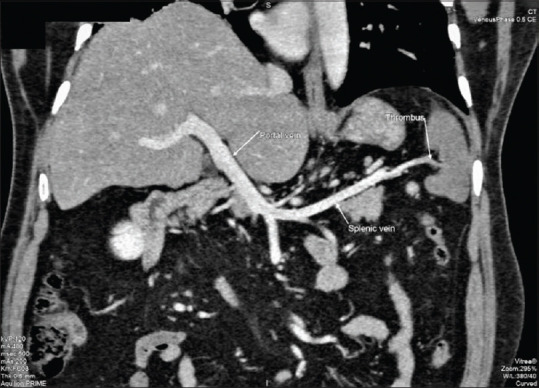

Mesenteric vascular thrombosis, typically of the superior mesenteric artery, is a frequent occurrence in patients with hypercoagulable conditions. Isolated involvement of the celiac artery is rare. Patients with celiac artery thrombosis can present with an acute abdomen or occasionally with acid peptic symptoms. A delay in diagnosis is associated with high rates of morbidity and mortality. We present a rare case of splenic infarction with celiac trunk thrombosis in a 54-year-old patient with underlying antiphospholipid (APLA) syndrome who presented with epigastric pain that was mistaken for symptoms of acid reflux.

Abstract Image